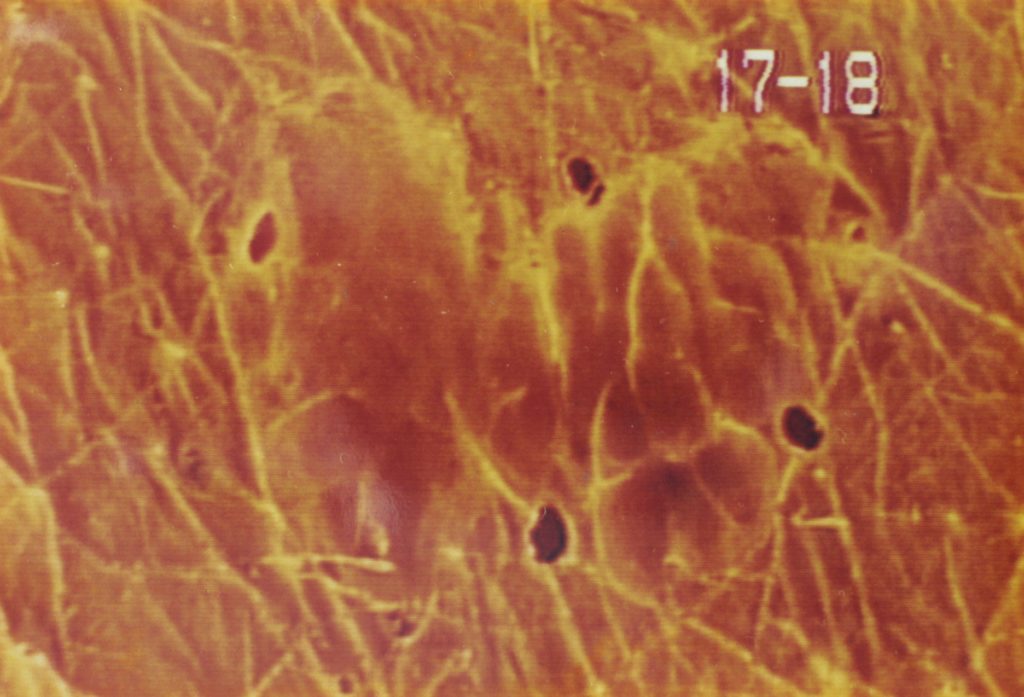

皮膚の変化

画像提供:皮膚科学研究所

右頬上のシワ 上x60 下x30

① 施術前

② 1回目の施術1週間後

③ 2回目の施術5日後

④ 3回目、施術4日後

⑤ 4回目、施術11日後